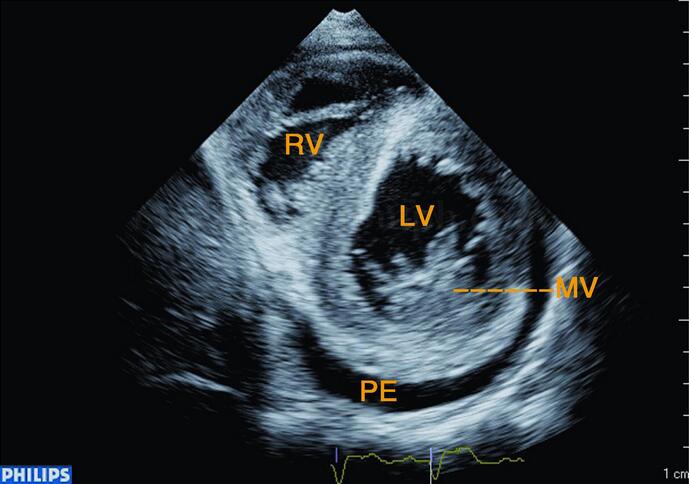

图2‐1‐217 左室短轴切面左室壁增厚,二尖瓣增厚,回声增强,左室后壁后中等量心包积液

图2‐1‐218 大血管短轴切面左房扩大,主动脉瓣、肺动脉瓣稍厚,回声稍强